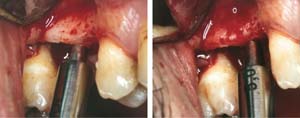

At the time of surgery, local infiltrative anesthesia was administered (lidocaine 2% with epinephrine, 1:100,000). A full-thickness mucoperiosteal flap was raised. The initial osteotomy was performed on midcrestal bone using a rose-headed bur. To prepare the osteotomy site for implant placement, sequential alternating osteotomes with variable conicity were used, drilling 2-mm shorter than the length of the implant to be placed (Figure 3A and Figure 3B). The implants presented initial primary stability (Figure 4), the cover screws were placed, and the implants were submerged for a healing period. The tissue was approximated, and the patient was instructed not to wear any denture or to place pressure on the healing site.

Figure 3A and Figure 3B Alternating osteotomes with variable conicity used to perform the alveolar remodeling in the area of tooth No. 24.